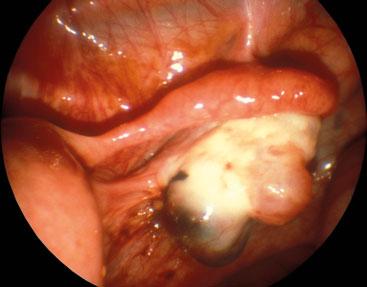

Infected Bartholin's Cyst

Bartholin's glands are located in the labia minora and the secretions produced help to lubricate the vagina. Problems with the gland usually occur between the age of 20-30 years. Presentation over 40 years of age is suggestive of malignancy. A cyst, which is usually painless, may develop in the gland. However, infection may occur which may cause symptoms such as dysparuenia and the development of a painful swelling. The cyst may discharge spontaneously. Infection is usually caused by organisms such as E. coli, Staphylococcus or Streptococcus. Less frequently, an infection may be caused by a sexually transmitted disease, most commonly chlamydia or neisseria. An infected cyst may be drained either by incision and passage of a catheter or by marsupialisation.